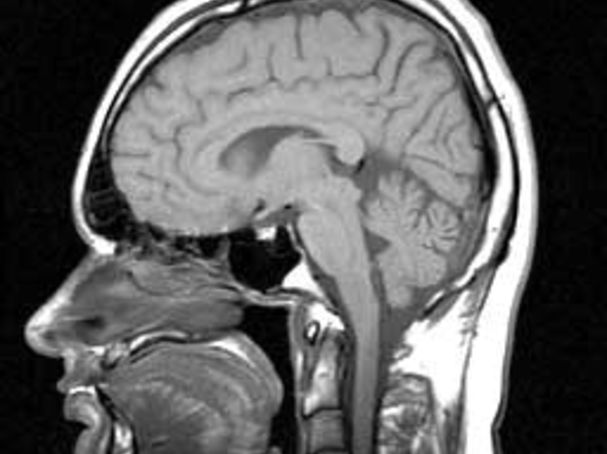

The Fallacy: Pain is Either Medical or Psychological. Pain is an integrated biopsychosocial experience. It is defined as a negative sensory and emotional experience. This means that to best treat pain, we must acknowledge that pain is distressing and, for many people, life-altering. Medical evaluation and care are important, and other approaches are also needed to address the full definition of pain. Individuals can become equipped with information, skills, and strategies that help them better manage the negative impacts of pain. This can help them reduce aspects of suffering, alter the trajectory of pain, and for some patients can even help reduce the need for medical care. This is "whole person" pain care.